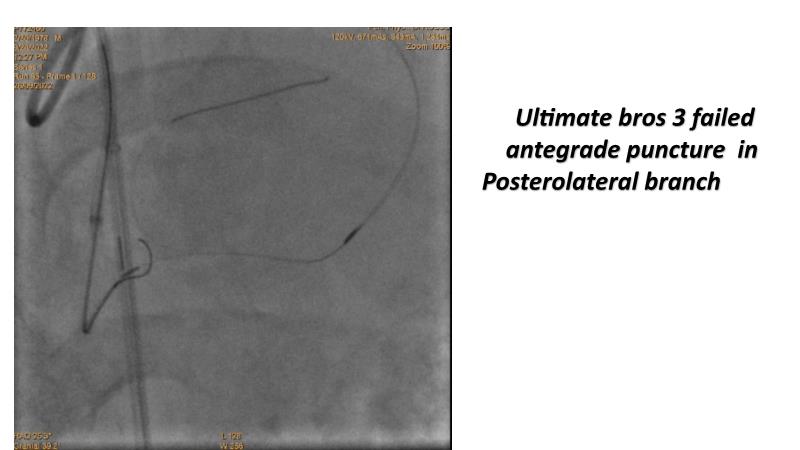

Thanks to the recorded complex CTO case shared in this session, learn how to perform ultra-low contrast PCI, learn what skills are required and tools available to perform ultra-low contrast coronary interventions in CTO, and become aware of the importance of relying on less contrast injections to guide PCI in complex CTO cases.

- To share and discuss a recorded complex CTO case showing how to perform ultra-low contrast PCI